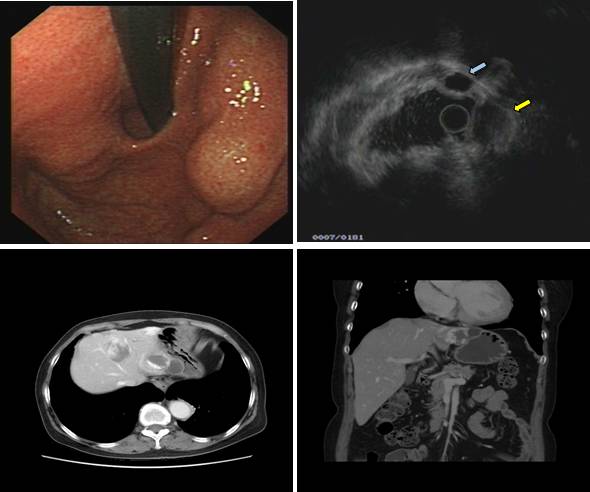

下面病例我们可以看到胃底粘膜下隆起,中央有凹陷(图A),外院CT也考虑胃底间质瘤(图B白色箭头处)。

患者拟手术来我院行超声内镜检查,小探头发现局部胃壁结构欠清,肿块内部为均匀点状回声(图 A),改环扫EUS探查见肿块后方为膈肌,内部为均匀点状回声,考虑副脾,该患者10年前因外伤切除脾脏,故诊断为脾脏切除后副脾代偿性增生外压。

嘱咐患者在我院复查CT检查,请放射科同事局部放大并重建后证实为副脾,故放弃手术。